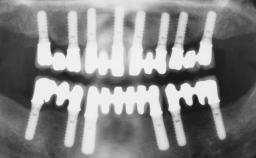

Immediate Loading of Six Implants in the Maxilla and Final Restoration with a Full-Arch Gold/Ceramic FDP Involving the Concept of Tilted Implants

# of Implants 6

Type of Implants One-Piece|Reduced-Diameter

Bone Augmentation Horizontal|Simultaneous

Defining Characteristics Fully edentulous upper jaw to be rehabilitated with four or more implants

Modality Fixed hybrid bridge on 5+ implants

Bone Volume Deficient horizontally, allowing simultaneous augumentation

Loading Protocol Immediate